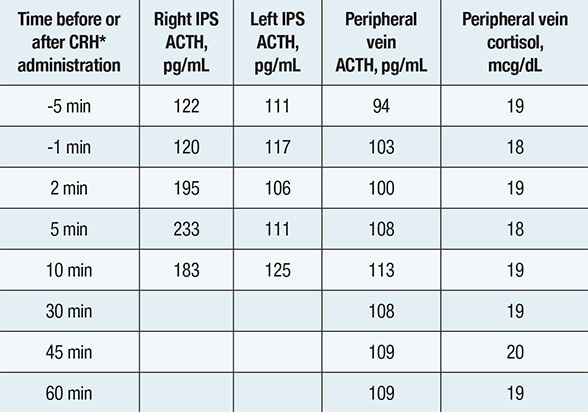

Inferior petrosal sinus (IPS) sampling

Inferior petrosal sinus (IPS) sampling

Inferior petrosal sinus (IPS) sampling showing comparable corticotropin (ACTH) concentrations in the left IPS, right IPS and peripheral vein — indicating a nonpituitary source of ACTH hypersecretion. *Corticotropin-releasing hormone

Biochemical evaluation confirmed corticotropin (ACTH)-dependent Cushing syndrome. Pituitary-directed MRI demonstrated a normal pituitary gland, and inferior petrosal sinus sampling indicated a nonpituitary source of ACTH secretion. In search of an ectopic neuroendocrine tumor, a chest CT scan identified a 7-by-5-mm nodule in the right lower lobe.